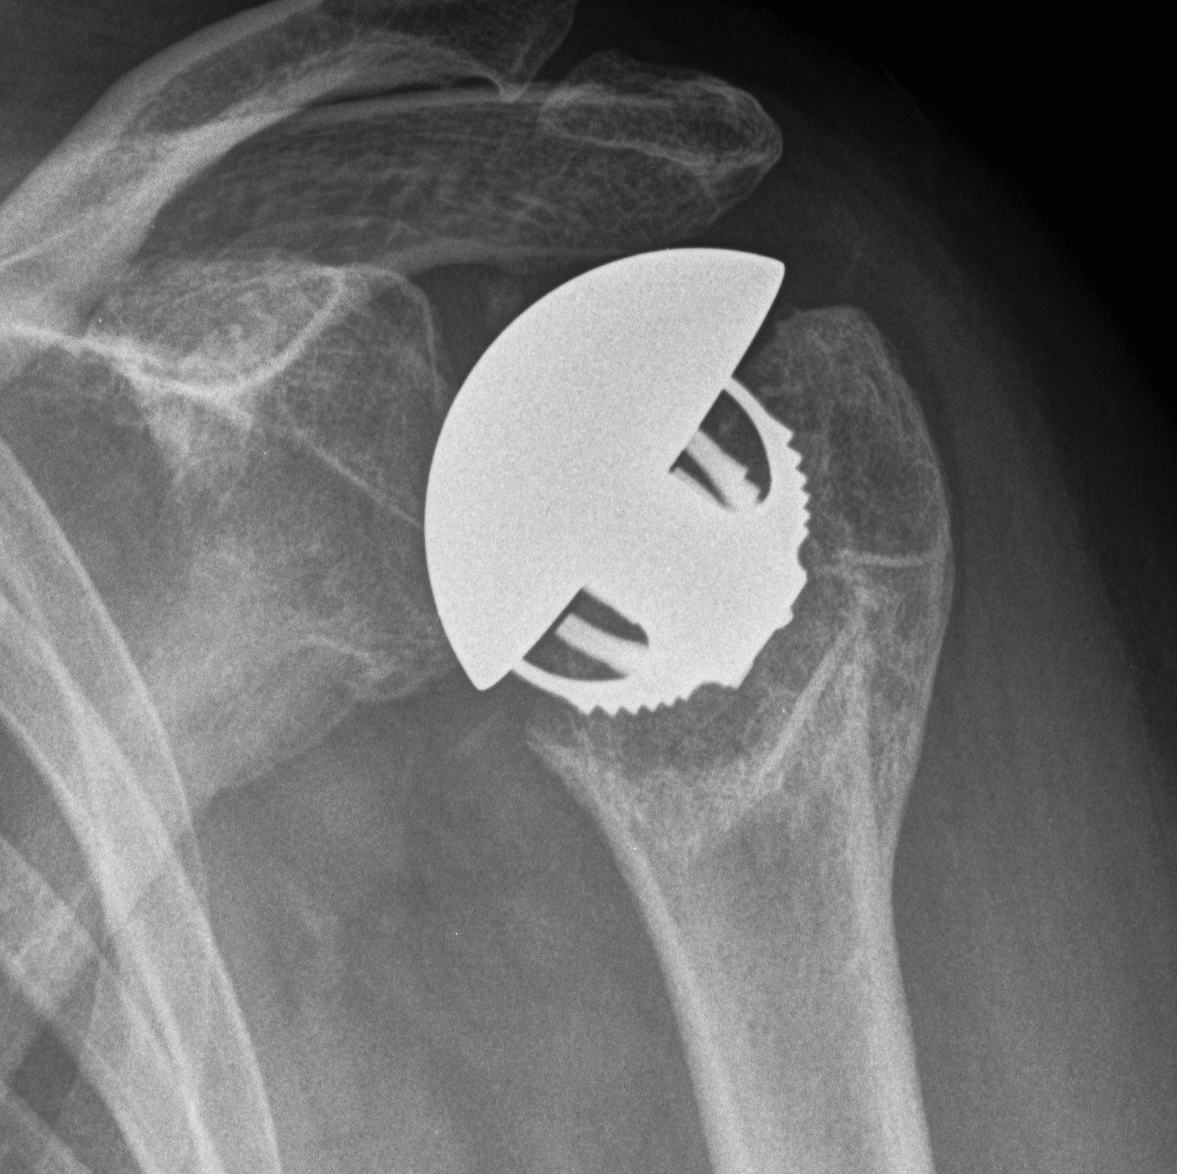

proximal humerus fracture Background ORIF with locking plate Arthroplasty Greater tuberosity fractures Lesser tuberosity fractures / avulsions Book traversal links for Proximal humerus fractures ‹ Pectoralis Major Tears Up Background ›